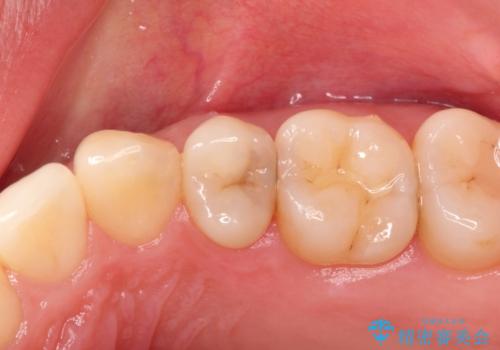

適合の良いセラミックインレー

- 定期検診して虫歯を認めたため、セラミックインレーにて修復治療を行なっております。

e-max プレスインレーにて修復治療を行っているため適合性及び審美性の高い治療を行うことができます